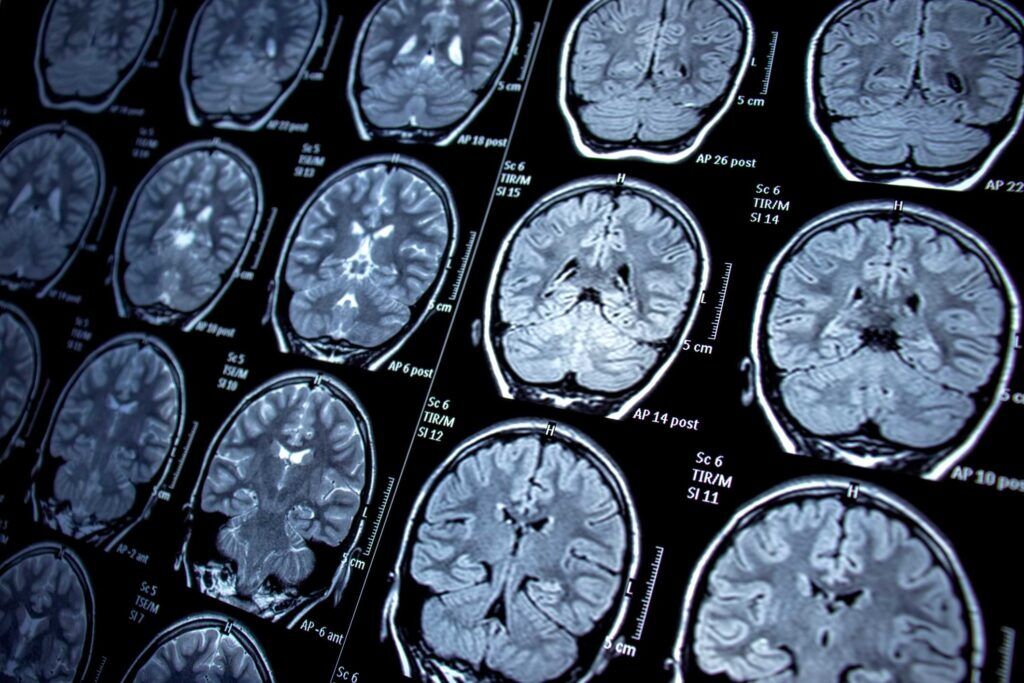

Neurological Disorders

MRI scans have emerged as a lifeline in identifying neurological conditions such as multiple sclerosis, strokes, and brain tumors at their earliest stages. In the case of strokes, recent research underscores the urgency of early detection. Approximately 2 million brain cells die every minute during a stroke (Dignity Health), highlighting the critical role that diagnostic imaging plays in expediting diagnosis and potentially life-saving intervention. There are several major manufacturers of MRI machines, including Siemens Healthineers, GE Healthcare, Philips Medical Systems, and Canon/Toshiba.

GE MRI Machines

- GE Signa Horizon LX 1.5T

- GE Signa Explorer 1.5T

- GE Signa Voyager 1.5T

- GE Signa Architect

- GE Ovation

- GE Discovery MR750 3T

- GE Optima MR450w 1.5T

- GE HDxT 3T

- GE Signa

Siemens MRI Machines

- Siemens Magnetom Aera 1.5T

- Siemens Magnetom Espree 1.5T

- Siemens Somatom Skyra 3T

- Siemens Magnetom Essenza 1.5T

Hitachi MRI Machines

- Hitachi Oasis Open 1.2T

- Hitachi Enchelon XL 1.5T

- Hitachi Airis Elite

Philips MRI Machines

- Philips Infinion 1.5T

- Philips Ingenia 1.5T & 3T

- Philips Achieva 1.5T & 3T

Canon (formerly Toshiba) MRI Machines

- Canon (formerly Toshiba) Titan 1.5T

- Canon (formerly Toshiba) Elan 1.5T

Esaote G-Scan Brio XP